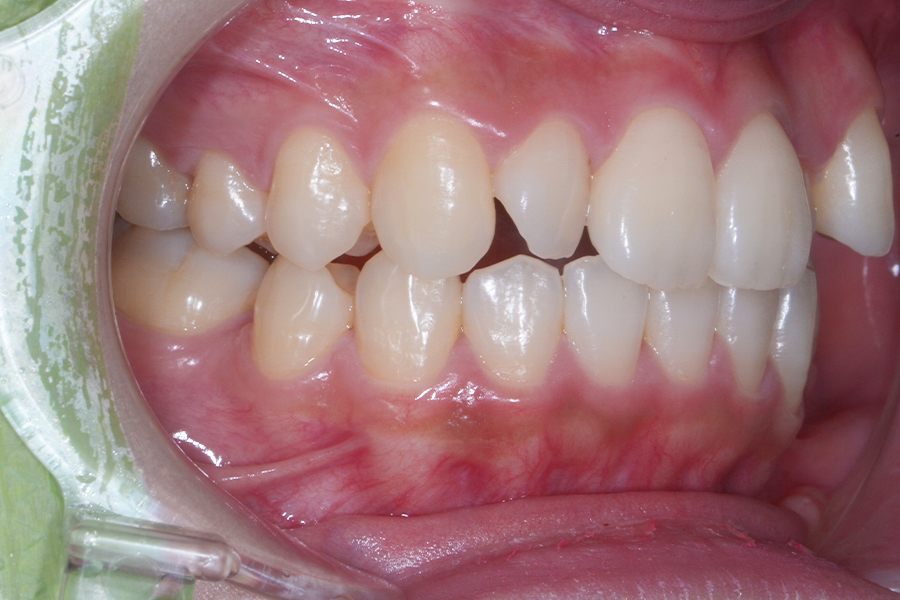

• 治療後